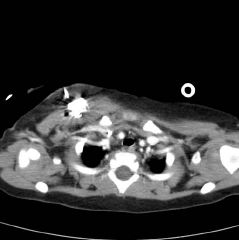

P.I= مشکل کودک از 50 روزگی شروع شده است. که با انجام

آزمایش ادرار

(U/A)

متوجه وجود هماچوری میکروسکوپی(30-35 گلبول قرمز) می شوند. علت انجام آنالیز ادراری

، این بوده که در سونوی 4 بعدی مادر در ماه هشتم حاملگی تورم در کلیه راست جنین

مشاهده شده بود. سونوگرافی در 50 روزگی نرمال بوده است. در 2 ماهگی هماچوری گروس هم

ایجاد می شود واز آن موقع تا کنون هماچوری میکروسکوپی ادامه داشته و هماچوری گروس

هم گاها دیده شده است.

در 2 ماهگی دفع پروتئین در ادرار در حد 2+ ایجاد می شود. تا 6 ماهگی هماچوری ادامه

می یابد و با انجام آزمایش پیگیری می شود.

یابد و با توجه به هماچوری و سایر علایم در تاریخ 12/2/88 بیوپسی کلیه انجام می

شود. در زمانی که برای بیوپسی کلیه بستری می شود ، یکسری ضایعات پوستی ماکولر هم

روی بدن ایجاد می شود.

جواب بیوپسی کلیه بیمارستان مفید:

Minimal mesengeal proliferation and focal glomerular sclerosis

Comment:in spite of absence of light microscopic positive findings membranous

lupus nephritis should be ruled out by EM and follow up the patient

جواب میکروسکپ الکترونی بیمارستان بقیه الله:

Thin glomerular basement membrane disease